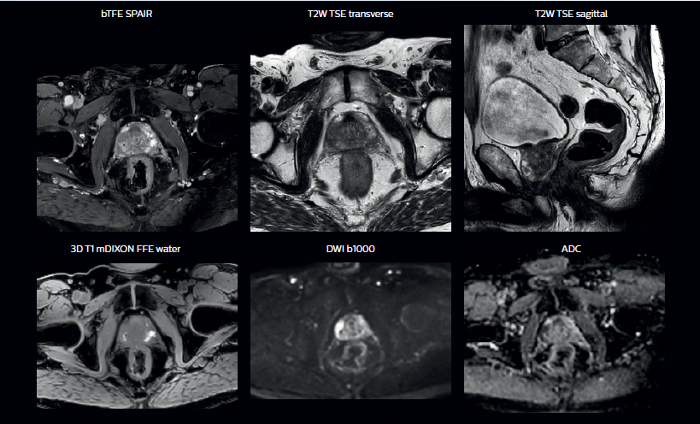

With its exceptional soft-tissue visualization capabilities and wide range of image contrasts, MRI has become a powerful tool to help more precisely define tumor boundaries. This is particularly important as it has been established that there is a high degree of uncertainty in target volume delineation, and it is even reported to represent the largest uncertainty in the entire radiotherapy process for most tumor sites**. Better visualization of the target area and nearby organs-at-risk is a key factor in enhancing target volume delineation. MRI’s expanding role also can be attributed to its functional imaging capabilities, which can inform both target characterization and treatment response.

With its superior soft tissue contrast compared to CT, MRI offers exquisite visualization of tumor boundaries and proximity to nearby critical structures.

In addition to anatomical imaging, MRI offers the ability to obtain functional information that is beneficial for tumor detection and delineation, and for response monitoring.

Diffusion-weighted imaging (DWI) for example depicts areas of high signal intensity in soft tissues that are indicative of the restricted water mobility (i.e., diffusion) of a tumor and can also be used to identify lymph nodes. Changes in the tissue’s or lesion’s apparent diffusion coefficient (ADC) can provide insights that help predict the tumor’s response to radiotherapy.

Ingenia MR-RT is a dedicated MR simulation platform that provides high quality, high contrast MR images acquired with the patient in treatment position. Designed for the needs of radiation oncology, this comprehensive solution provides the tools and software needed for versatile and efficient imaging for radiotherapy planning.

Innovative MR-only simulation helps you use MRI as the primary imaging modality for planning prostate cancer patients’ treatment, thereby eliminating tedious and error-prone CT-MR registration and simplifying workflows. Available as a plug-in extension to the Ingenia MR-RT platform, MR-only simulation provides high contrast anatomical MR images for target delineation and the density information for dose calculations typically provided by CT.